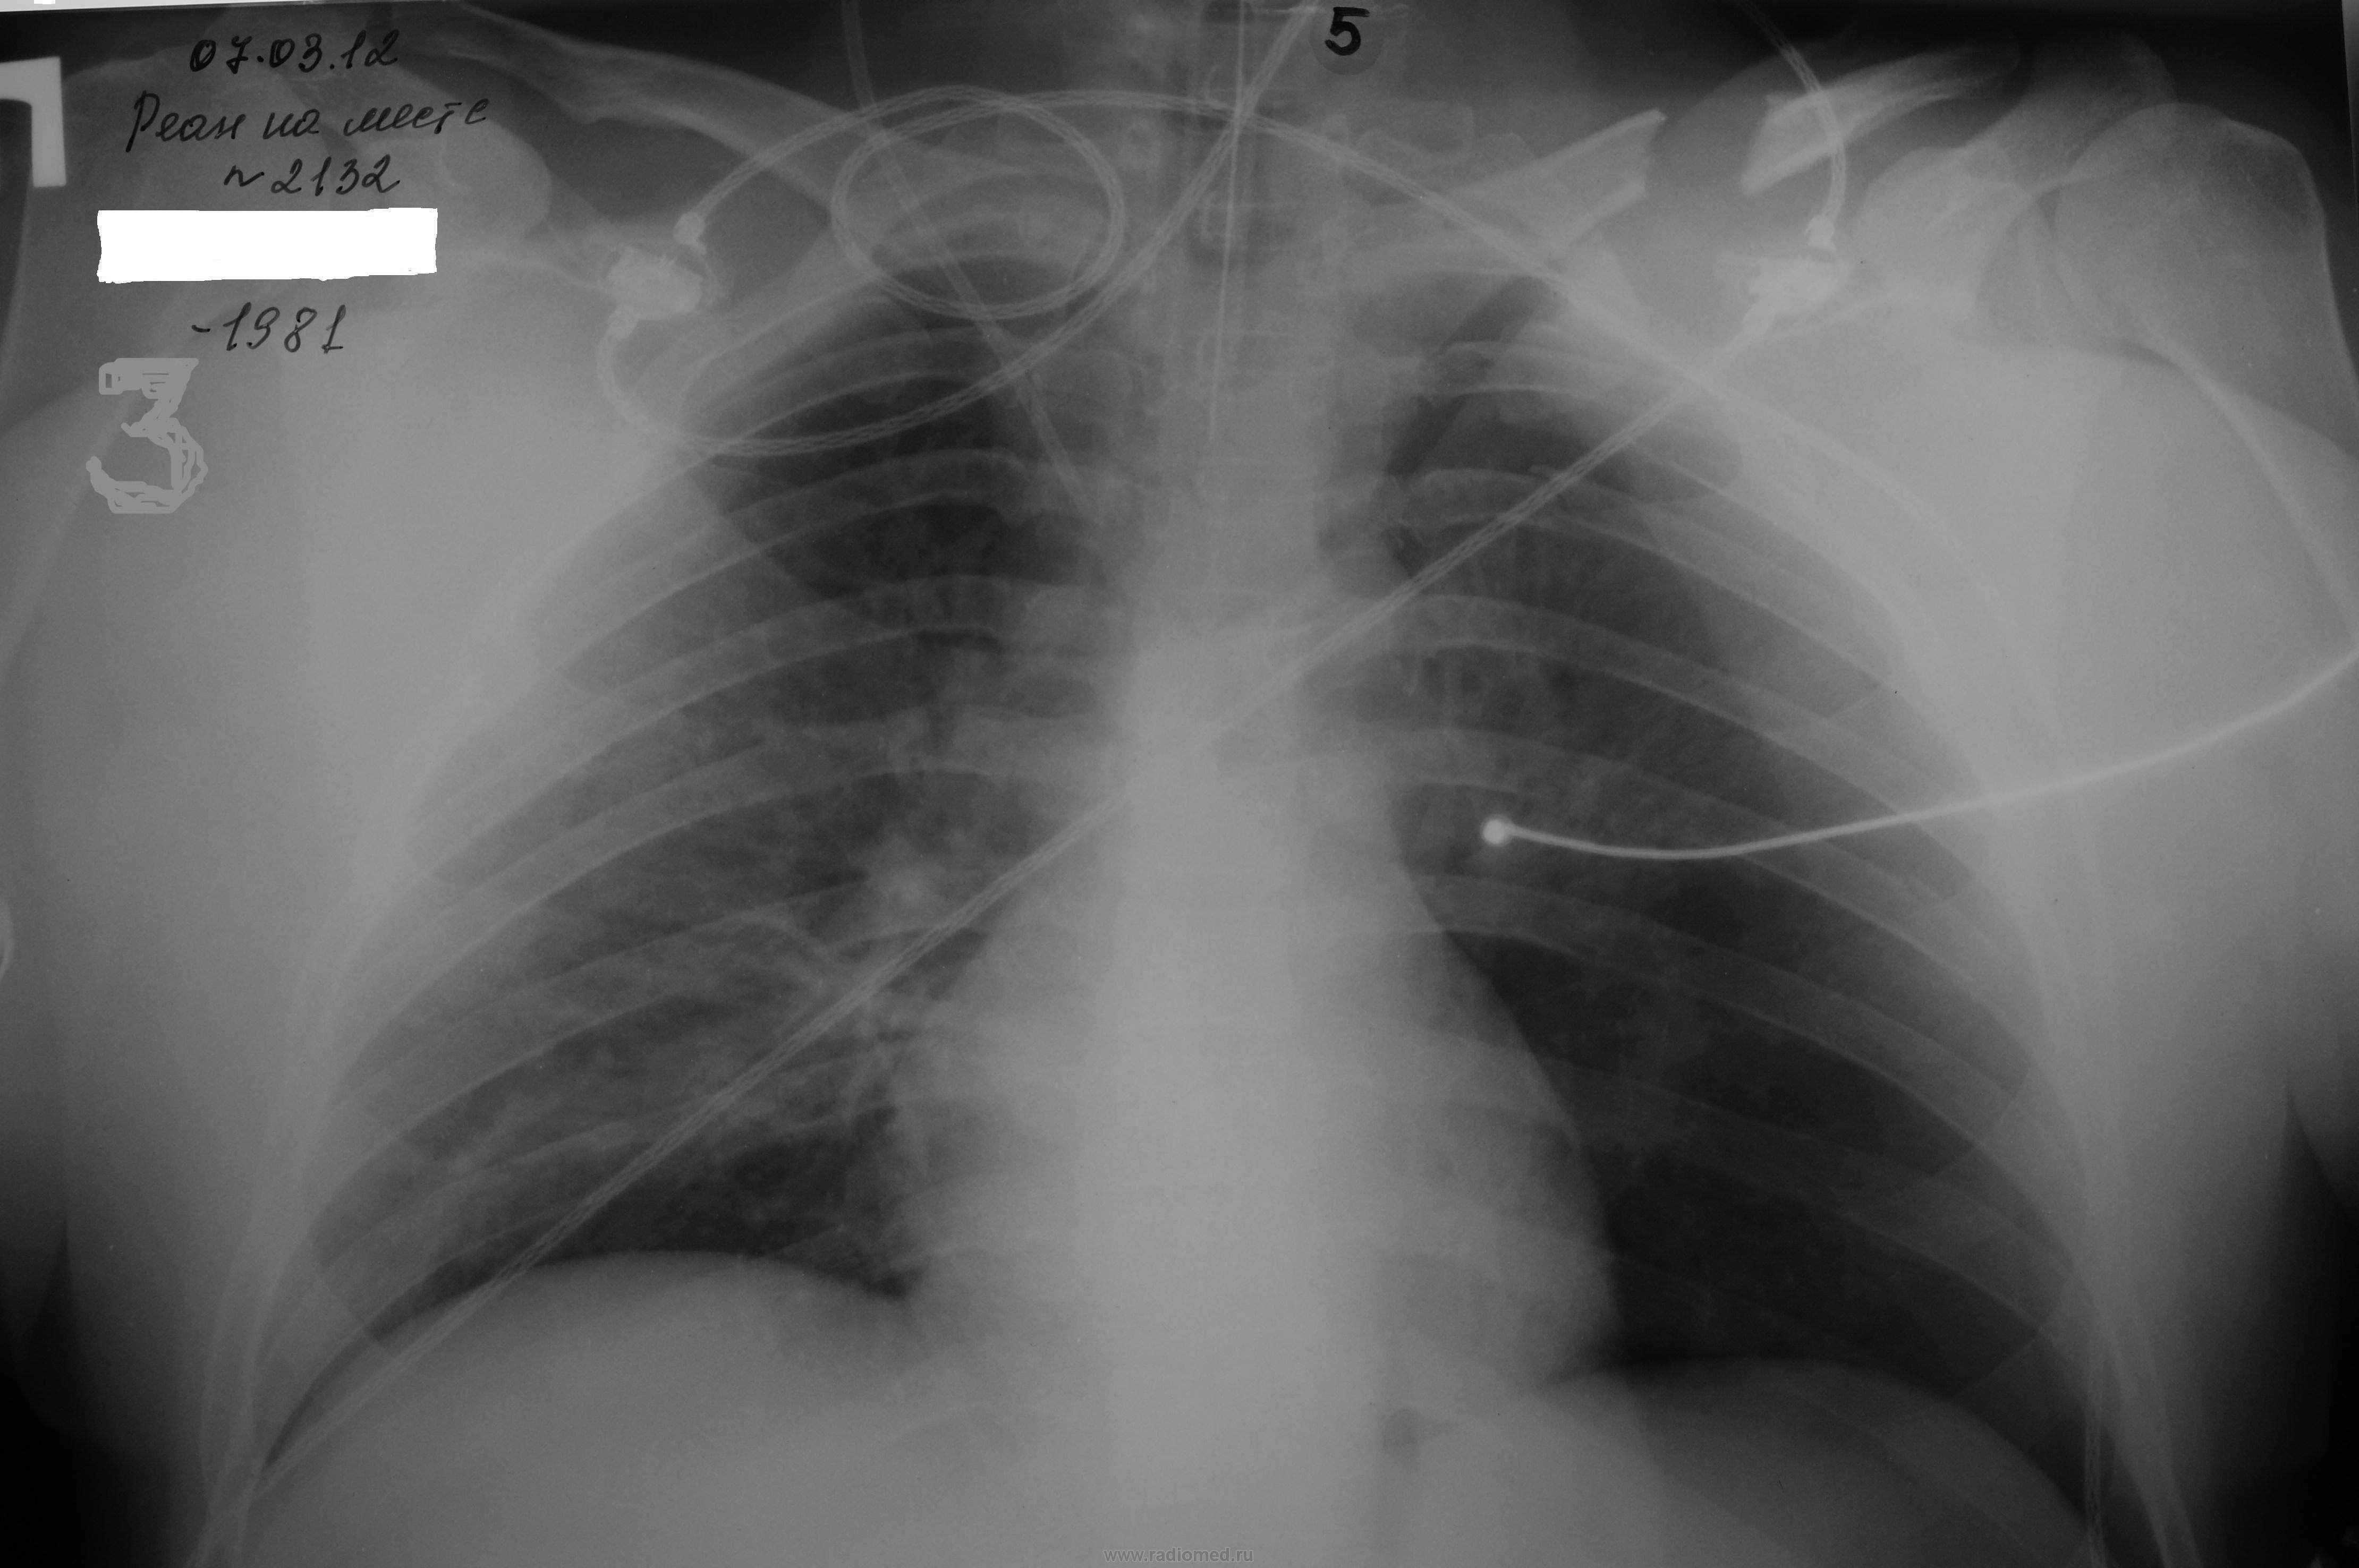

Ниже приводится рентгенограммы трех пациентов с напряженным пневмотораксом, у которых не было заметного ослабления дыхательных шумов на стороне пневмоторакса. Тогда как ненапряженный пневмоторакс и напряженный пневмоторакс (с выраженным колабированием легких), как правило, дает четкое ослабление дыхательных шумов.

Если не ошибаюсь, на всех представленных рентгенограммах пневмоторакс не тотальный. Хотя бы местный, но контакт легкого с грудной стенкой прослеживается. Надо полагать, отсюда и аускультативные данные, которые феноменом в данном случае назвать сложно...

При напряженном пневмотораксе везде описывается ослабление и отсутствие дыхание на стороне патологии. Оно, как правило, так и бывает, потому что при напряженном пневмотораксе чаще легкое колабируется более чем на 1/3 и до полного колапса. В обсуждаемых случаях напряженный пневмоторакс нетипичный - краевой. И в этом кроется объяснение аускультативного феномена.

Не вижу признаков напряженного пневмоторакса, тень средостения на месте, межреберные промежутки не расширены, диафрагма не уплощена. Почему решили, что это напряженный пневмоторакс?

Напряженный пневмоторакс по степени напряжения воздуха и скорости его нарастания бывает тоже разный. Если считать напряженным только те пневмотораксы, которые в первые часы травмы явно смещают средостение, то куда отнести выше приведенные (клапанные), которые нарастали постепенно и вызывали дыхательную недостаточность?

В первом случае дыхание с обеих сторон практически одинаковое (больной в положении на спине на скелетном вытяжении). Сначало было желание не трогать малый краевой пневмоторакс либо ограничиться пункцией. Но больной жаловался на затрудненное дыхание и приступы удушья. И когда не удалось выслушать тоны сердца ни справа, ни слева, сомнений в необходимости дренирования не было. Тоны сердца появились сразу после дренирования.

"Парадокс" в том, что при хорошем проведении дыхательных шумов, не были слышны тоны сердца. Пневмоторакс, который вызывает дыхательную недостаточность и скрывает тоны сердца не может не отразиться на проведении и дыхательных шумов спереди. Только напряженностью воздуха можно попытаться обяснить этот феномен.

Честно скажу, что только после второго случая, когда явная клиника напряженного краевого пневмотракса (тоны сердца были слышны, но только смещены вправо, пульс с появлением пневмоторакса вырос с 80 до 160 уд, высокая кислородо зависимость - и все это купировалось после дренирования) также протекало с симметричной аускультативной картиной - был оценен как напряженный пневмоторакс и первый случай.